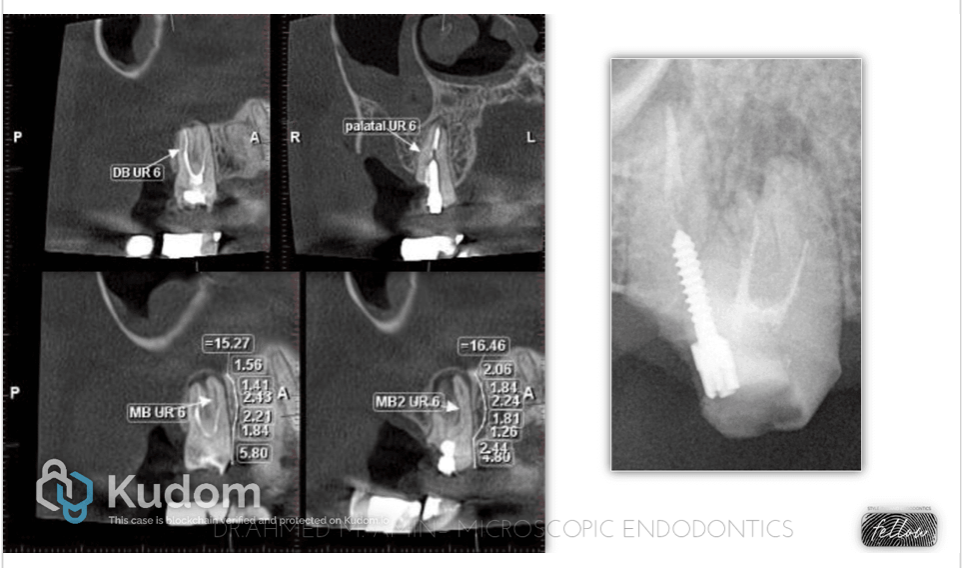

Fig. 4

1st & 2nd Xray : First MTA Apical plug

3rd Xray : Obturation the rest of the canal with WVC + Bio C sealer

4th Xray : Final Obturation

5th Xray : Final Restoration